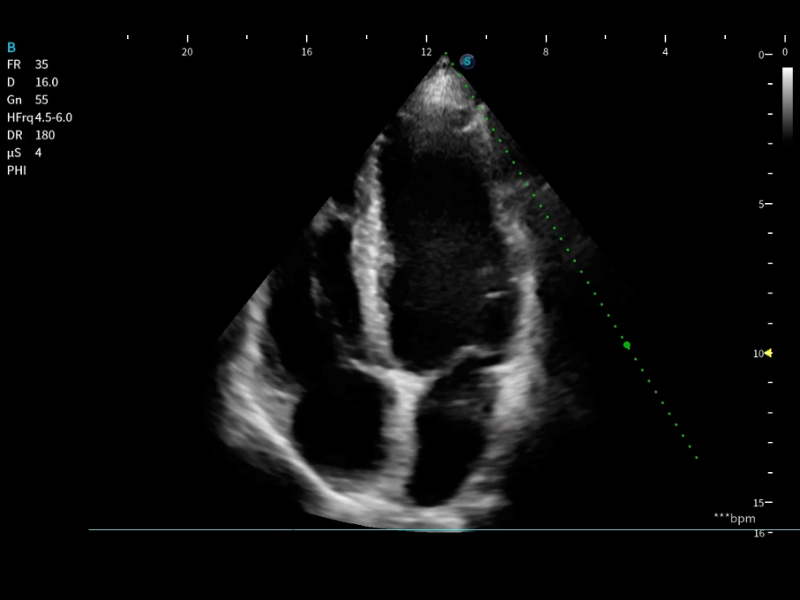

便携式彩色多普勒超声诊断系统

作为开立医疗全新打造的高端床旁笔记本超声,E11不仅具备卓越的图像质量,同时搭载全面高效的自动测量工具,助力医生实现更快速、更精准的床旁诊断。

E11搭载了丰富的自动化测量工具,以及专为POC科室定制的高级功能;同时配备了为急诊医师量身打造的 SonoFast急重症超声流程,以帮助临床医生最大限度的提升工作效率